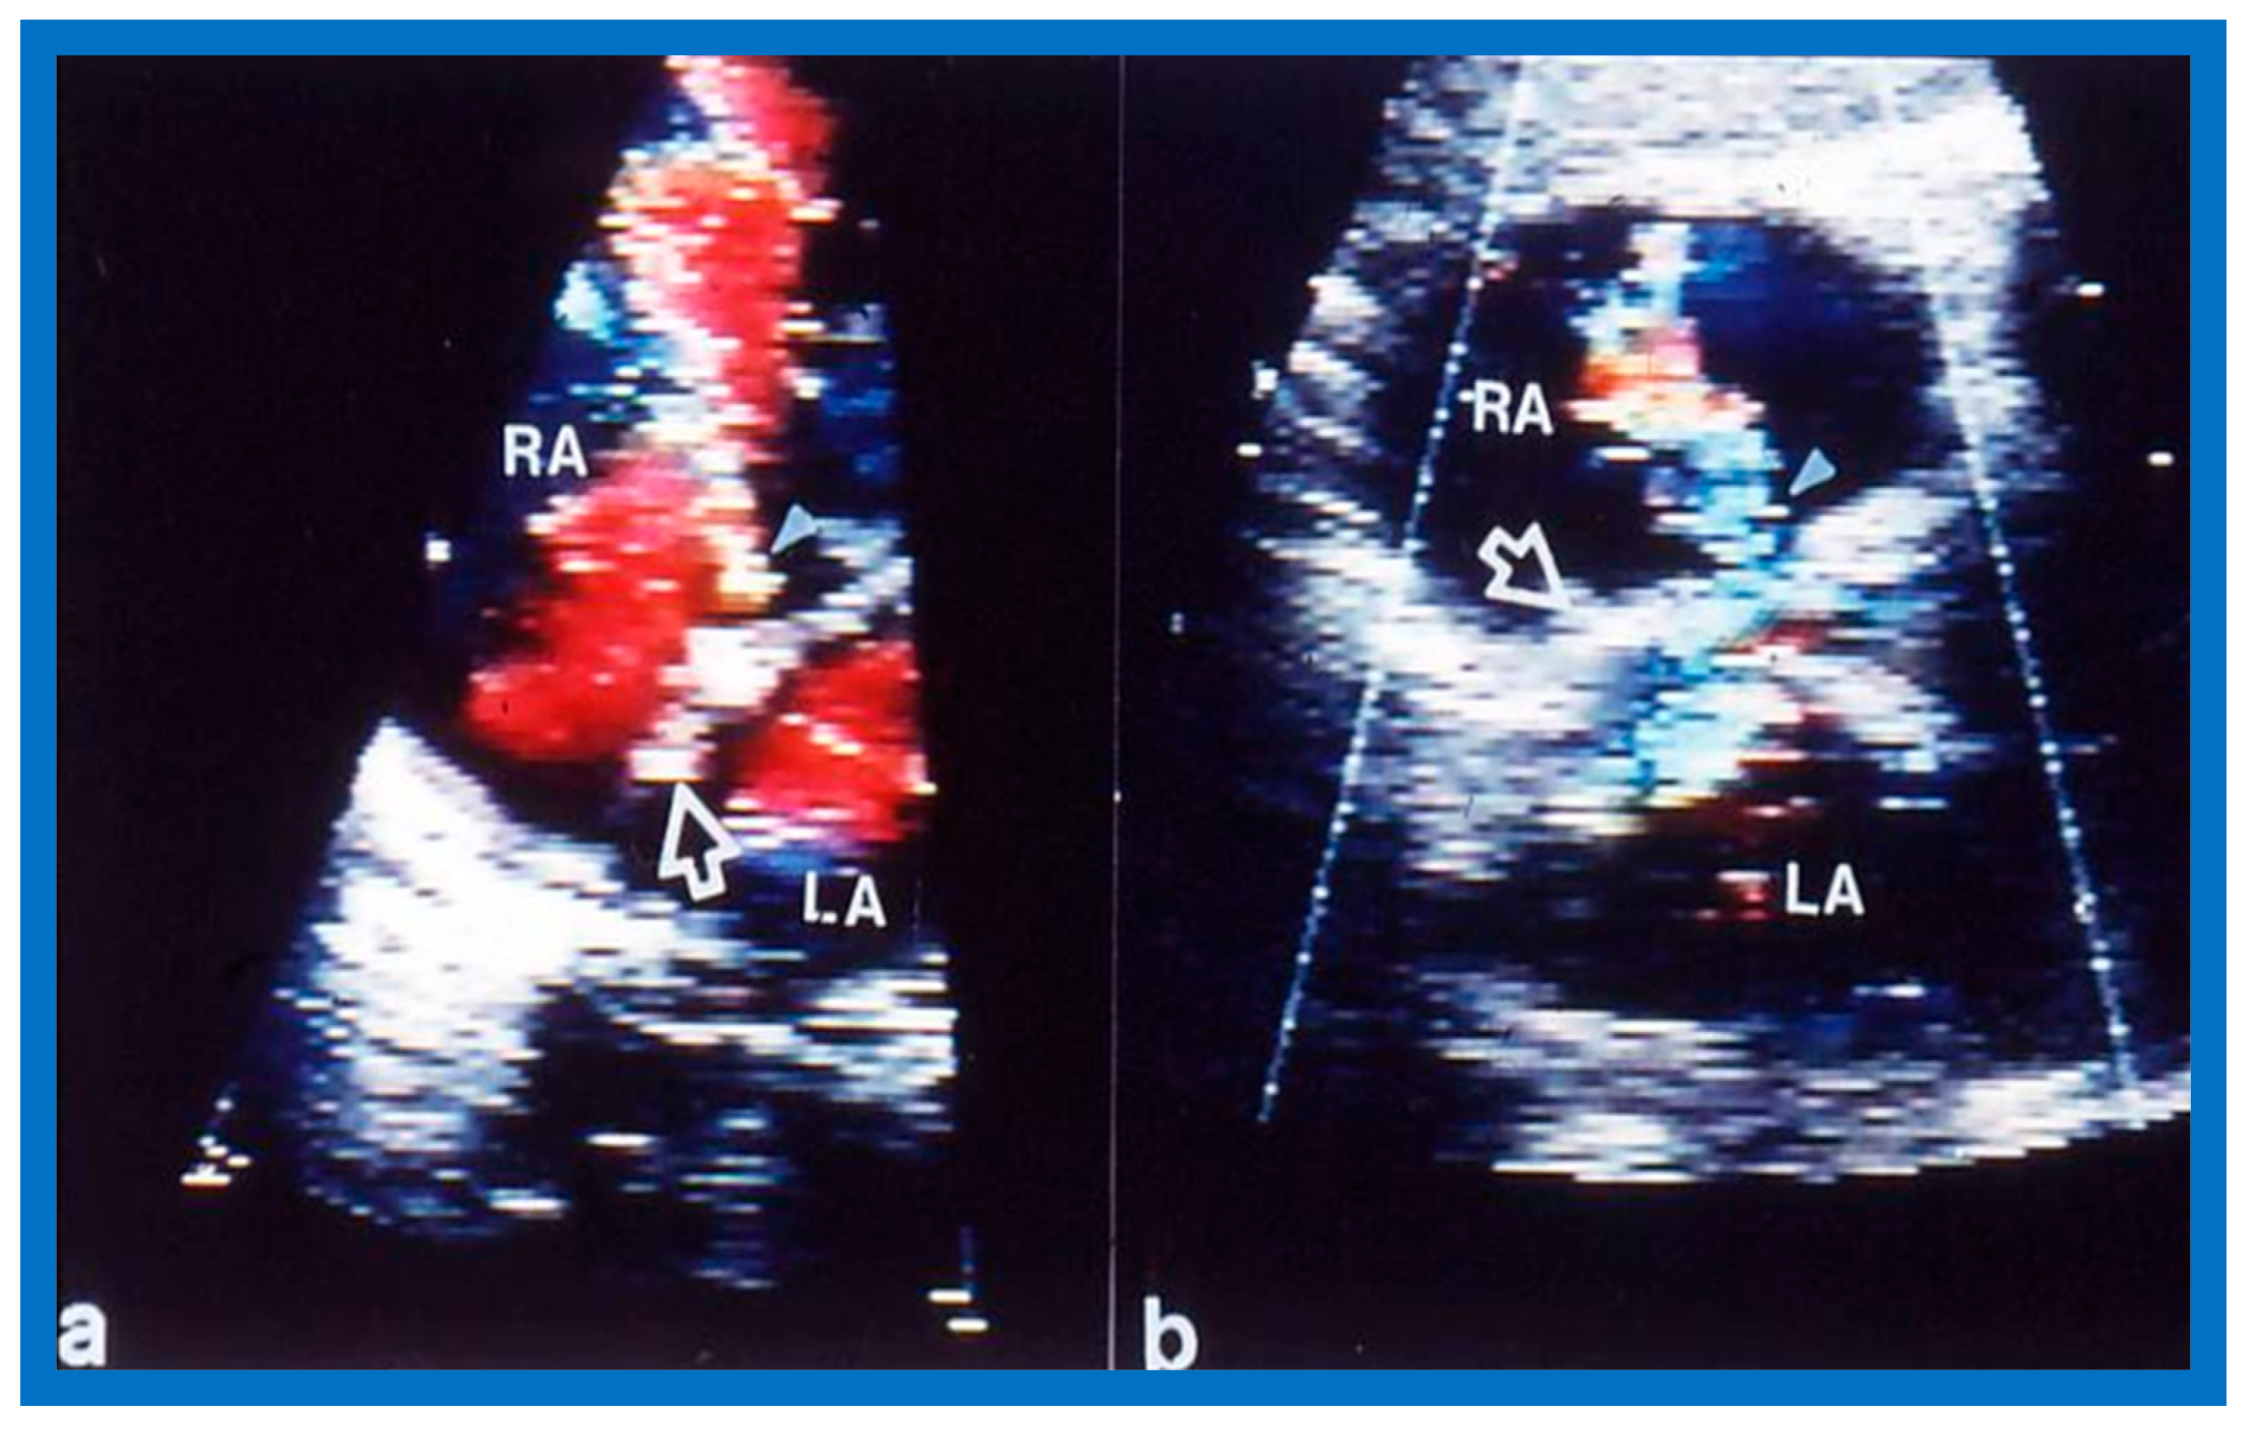

2. Diagnosis

6. TEE and ICE

- Singh, G.K.; Marino, C.; Rao, P.S. Ultrasound as an adjunct to cardiac intervention in the pediatric patient. J. Invasive Cardiol. 1996, 8, 341–349. [Google Scholar] [PubMed]